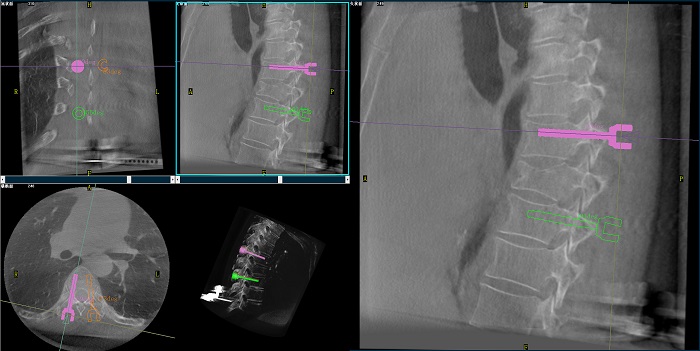

②機(jī)器人輔助胸椎手術(shù)操作難點(diǎn)之路徑規(guī)劃

人體胸椎的椎弓根較腰椎更狹窄,周圍有重要的神經(jīng)和血管,選擇合適尺寸和長(zhǎng)度的螺釘至關(guān)重要。螺釘過(guò)粗可能損傷椎弓根,過(guò)細(xì)容易發(fā)生形變,固定強(qiáng)度不夠;螺釘過(guò)長(zhǎng)可能穿透椎體前緣,造成損傷,過(guò)短則固定不牢。

普愛醫(yī)療手術(shù)導(dǎo)航定位系統(tǒng)解決方案

使用機(jī)器人輔助手術(shù),醫(yī)生不僅可以在影像的引導(dǎo)下,一次性完成多枚螺釘?shù)穆窂揭?guī)劃,提高手術(shù)效率,而且可以精確地選擇螺釘?shù)慕嵌取⒅睆胶烷L(zhǎng)度,提高手術(shù)的成功率。